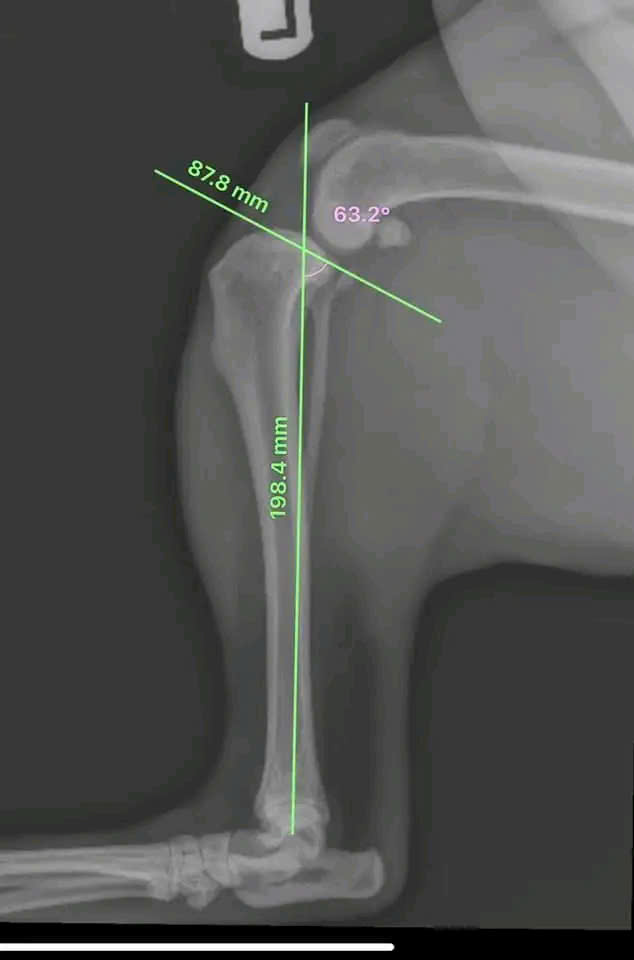

Siêu âm & X-quang

Chẩn đoán hình ảnh kỹ thuật số chính xác

Bác sĩ giàu kinh nghiệm, chuyên điều trị các case bệnh khó, từ nội ngoại khoa đến chấn thương chỉnh hình

Máy móc, thiết bị y tế tiên tiến, quy trình chẩn đoán nhanh chóng và chính xác